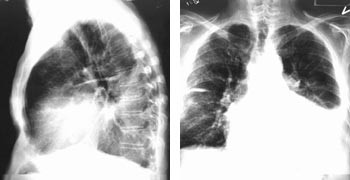

Pasient 1 er en 72 år gammel mann med idiopatisk dilatert kardiomyopati. Til tross for medikamentell behandling har hjertesvikten vist en jevn progrediering til funksjonsklasse IV (tab 1, 2). Han ble pleuratappet tre ganger for 1 300 – 2 000 ml pleuravæske (fig 4). Det ble implantert InSyncTM permanent pacemaker etter den angitte metoden (tab 3). Som vist på figur 5, fører biventrikulær pacing til en betydelig reduksjon av QRS-bredden sammenliknet med høyre ventrikkel-pacing. Det kom ganske snart betydelig subjektiv bedring av hans hjertesvikt til funksjonsklasse II, og han har hittil vært ute av sykehuset i 13 måneder. Det har vært en jevn reduksjon av hjertestørrelsen og vedvarende bedring av venstre ventrikkels ejeksjonsfraksjon (tab 4, 5). Røntgen thorax har vist avtakende hjertestørrelse (fig 6). Undersøkelse av vev med farge vevsdoppler ekkokardiografi-målinger viser bedret synkronisering av kontraksjonen under biventrikulær pacing. Man har også sett normalisering av serum-natriumkonsentrasjonen og bedring av en forhøyet serum-kreatininverdi.

Den første av våre pasienter har vært behandlet med pacemaker i 13 måneder. Det har vært en tiltakende bedring av hans kardiale funksjonskapasitet, bedring av venstre ventrikkels ejeksjonsfraksjon fra 15 % til 38 %, samtidig betydelig reduksjon av venstre ventrikkels endediastoliske dimensjon og regress av kronisk pleuravæske (tab 4, fig 4, 6). Pasienten har ifølge eget utsagn fått et helt nytt liv. Han steller seg selv som enkemann, utfører alle daglige gjøremål og har ikke vært innlagt i sykehus siden han fikk implantert pacemaker. For at biventrikulær pacing skal virke gunstig hemodynamisk, må det være kontinuerlig pacemakerstimulering både av høyre og venstre ventrikkel, for det er først da man resynkroniserer kontraksjonen. Hos pasienter med atrieflimmer med rask overledning til ventriklene og med spontanrytme i ventriklene (pasient 1), må man i noen tilfeller gjøre radiofrekvensablasjon av atrioventrikulærknuten slik at man oppnår kontinuerlig pacemakerrytme. Hos pasienter med sinusrytme i atriet, må atrioventrikulærintervallet i pacemakeren programmeres slik at man oppnår maksimal økning av slagvolumet under pacing og samtidig har kontinuerlig stimulering av ventriklene (14).